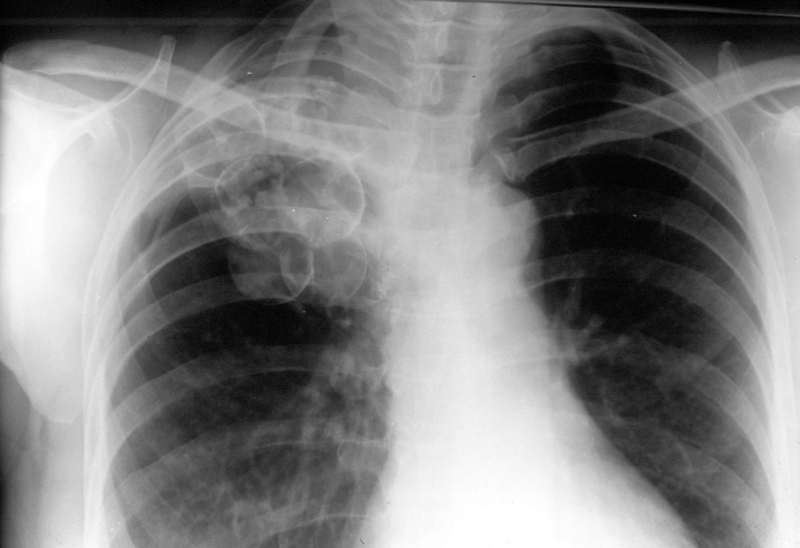

Astfel, debutul treptat şi semnele de boală „banale” întârzie destul de mult diagnosticul. Pacienţii ajung la spital cu leziuni pulmonare foarte extinse, ceea ce îngreunează în mod simţitor tratamentul. Toate aceste simptome evoluează ondulator, ceea ce înseamnă că perioadele simptomatice sunt urmate de intervale de timp asimptomatice.

Dr. Tănase recomandă ca pacientul să se prezinte la medic în momentul în care sesizează modificări ale stării de sănătate. Diagnosticul se pune foarte uşor, printr-un examen bacteriologic al sputei, destinat evidenţierii bacilului Koch şi printr-un examen radiologic normal.